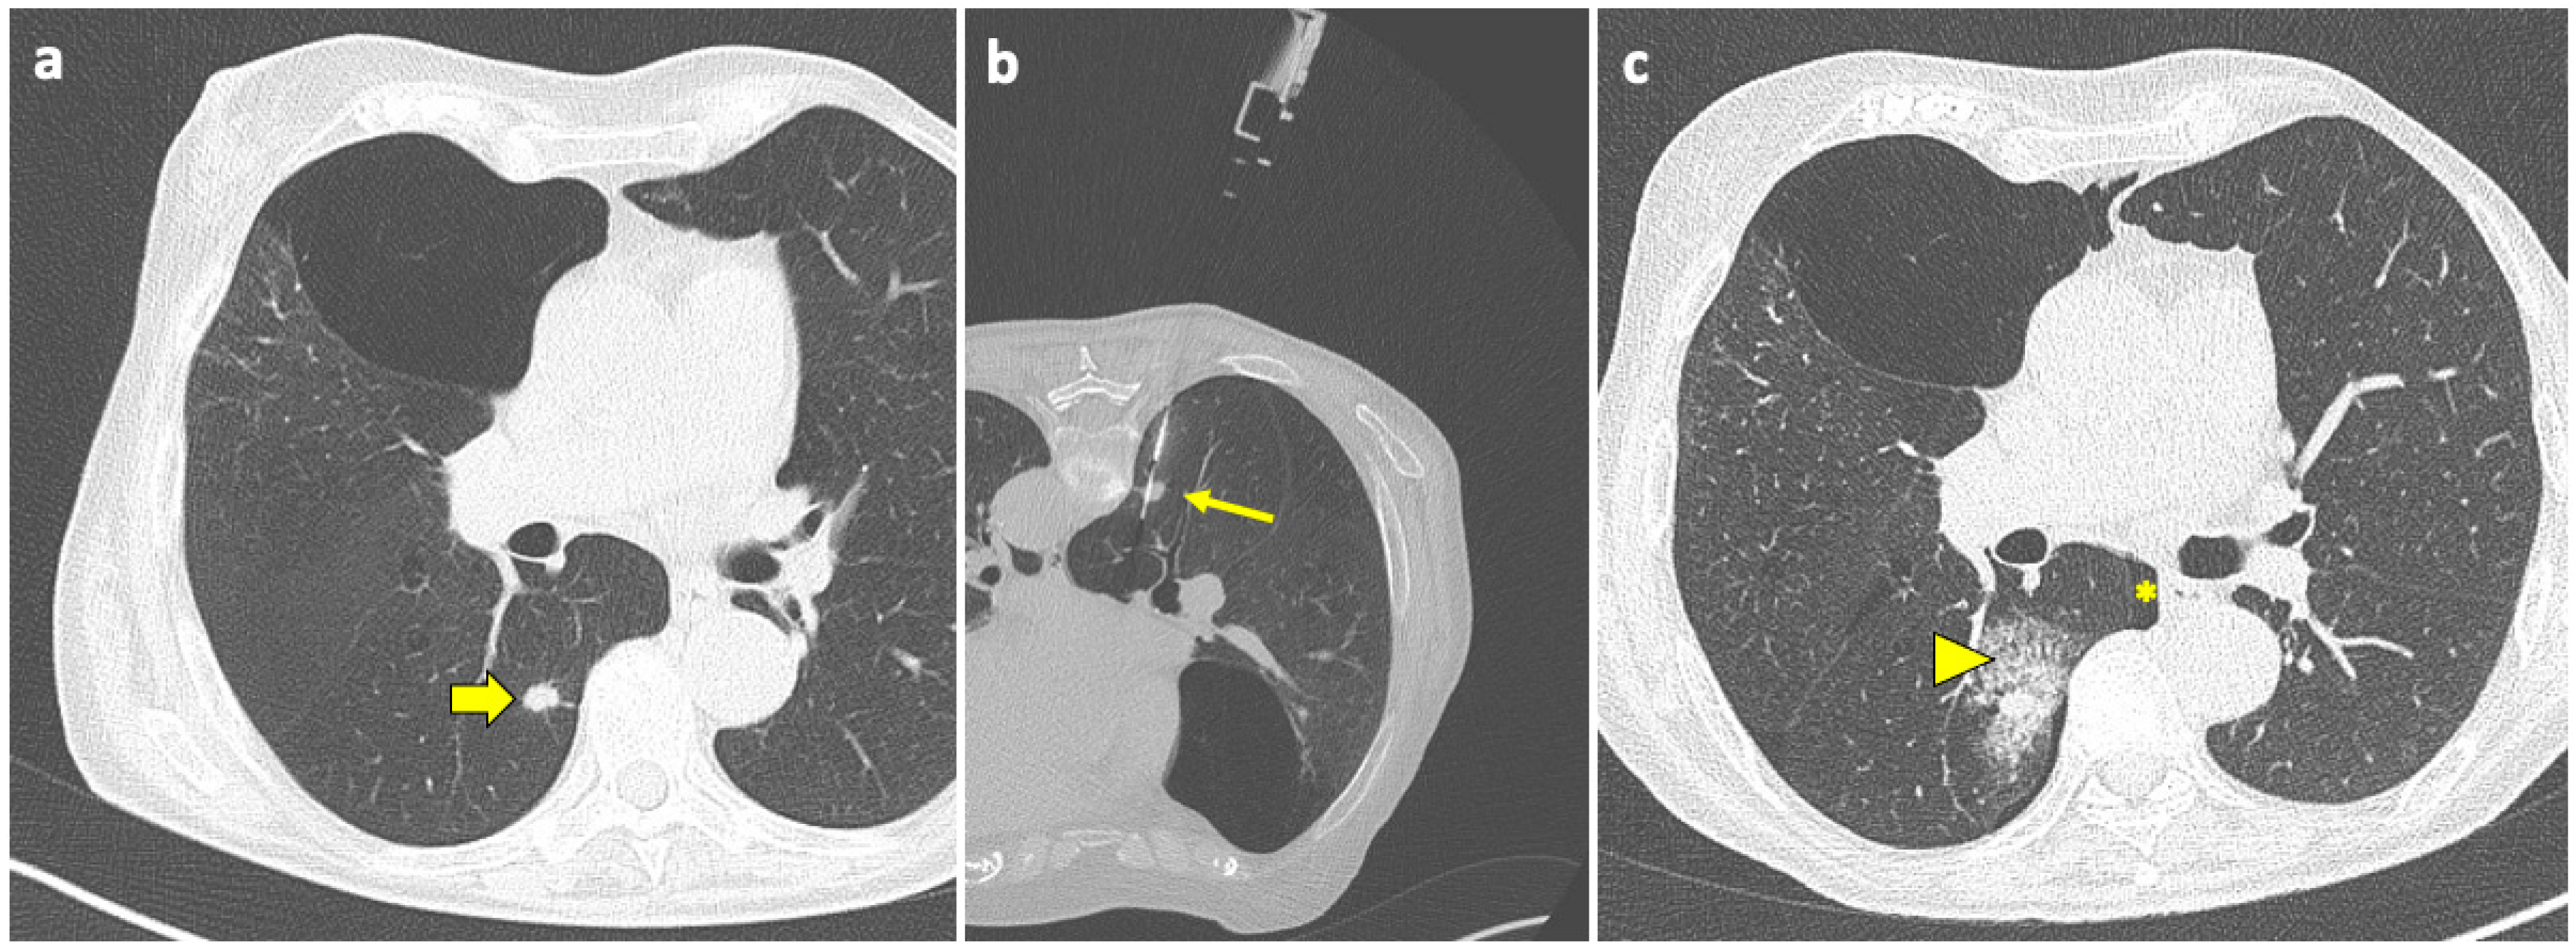

Patient with moderate–severe PNX and/or breathlessness require active intervention, with simple aspiration being suggested as initial treatment [91]. If still in place, the coaxial cannula used for the biopsy can be retracted back into the pleural space and used for aspiration; otherwise, it can be reinserted near the biopsy site. An example of manual aspiration is shown in Figure 2.

Manual aspiration is efficient at preventing PNX advancement because it creates an apposition between the visceral and the parietal pleura. When PNX develops despite manual aspiration, a chest tube is needed [85]; a small-bore catheter (10–14 F) should be placed for chest drainage [84,91].

Pulmonary hemorrhage is the second most common complication after PTLB, with a prevalence ranging from 4 to 27% [94]. In the majority of cases, this complication is mild and only detected on the post-biopsy CT scans as ground-glass opacity (GGO) around the lesion or along the needle tract, representing an alveolar hemorrhage in clinically asymptomatic patients, as shown in Figure 3.

Typically, no treatment is required, and the only measure that should be adopted is to position the patient with biopsy-side-down to avoid the aspiration of blood into the unaffected lung. When PH becomes symptomatic or a higher-grade PH arises, oxygen and pro-coagulative therapy may be required.